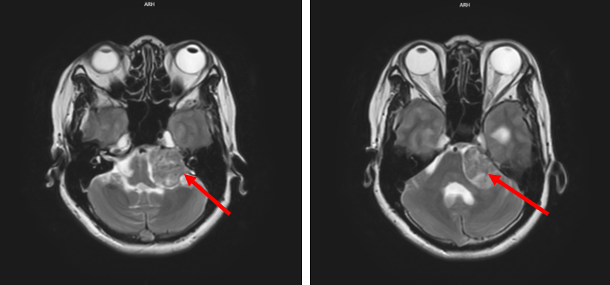

Sau phẫu thuật:

Hình 2: Hình ảnh khối vị trí góc cầu tiểu não trái sau phẫu thuật còn ngấm thuốc vùng vỏ, giảm kích thước so với trước khi phẫu thuật.